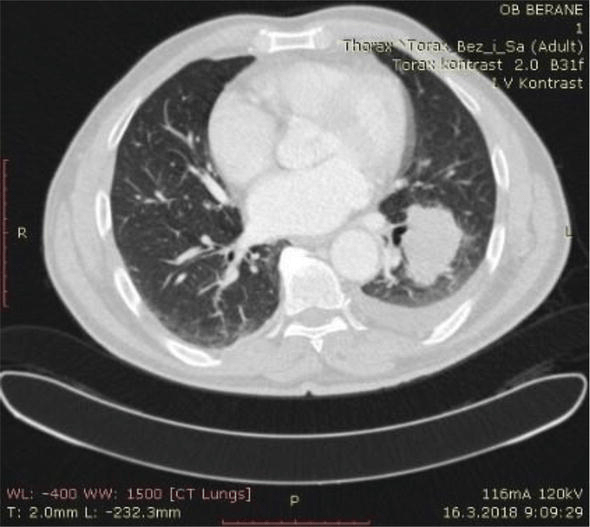

Pleural Effusions in Lung Cancer Detection and Treatment IntechOpen Why Does Cancer Cause Pleural Effusion Cancer cells cause the body to make too much pleural fluid, and they stop the fluid. Pleural effusion is the buildup of excess fluid between the layers of the pleura around your lungs. Pleural effusion is a common symptom of lung cancer and other cancers. Learn about the causes, symptoms, diagnosis and treatment of malignant pleural effusion, a complication of. Why Does Cancer Cause Pleural Effusion.